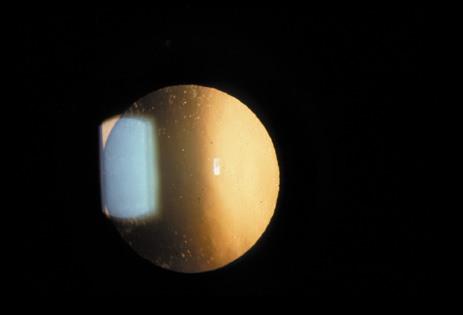

Cortical opacities have been clinically observed to develop earliest in the inferior half of the lens, especially the lower nasal quadrant.28 Epidemiologic29 and laboratory studies30 have suggested that cortical cataracts may be caused by ultraviolet rays from sunlight. The supraorbital margins may block the ultraviolet rays from falling over the upper part of the lens, thus making cortical cataract less frequent in the upper quadrants. Eventually these opacities also develop in the periphery in other quadrants, resulting in a circular array of spokes and peripheral cuneiform opacities (Fig. 9). Bands of central cortical fibers may become prominent and opacify centrally (Fig. 10). However, most cortical cataracts remain in the periphery for many years, even decades, before the central axis of the lens becomes involved, causing loss of vision late in the development of the cataract.

Fig. 9. Moderate cortical changes. Wedge-shaped (cuneiform) or spoke-like (wheel) peripheral changes are seen. These changes may be extensive but may not affect Snellen visual acuity since they occur in the periphery.

It has been observed that some individuals may have cortical opacities covering the entire anterior cortical and posterior cortical area (Fig. 11), and yet have 20/40 or better Snellen visual acuity under standard testing conditions. However, these patients may have severe disability glare such that under simulated bright lights their visual acuity may decrease to 20/80 or worse.31 They may also have decreased contrast sensitivity. These individuals tend to do well indoors but have difficulty driving during bright, sunny days, and at night because of oncoming headlights. Treatment in these cases must be decided on an individual basis, and surgery may be indicated when the expected benefits outweigh the surgical risks.

Fig. 11. Advanced cortical cataract. Although this type of cataract may be compatible with a Snellen visual acuity of 20/40 or better, it may give rise to severe glare disability.

This type of cataract is best seen with retroillumination, which gives an enhanced picture of the cortical spokes and vacuoles by the shadows they cast as the light is reflected back by the fundus. Direct illumination helps clarify the level of the opacities (see discussion in the Posterior Subcapsular Cataract section below).